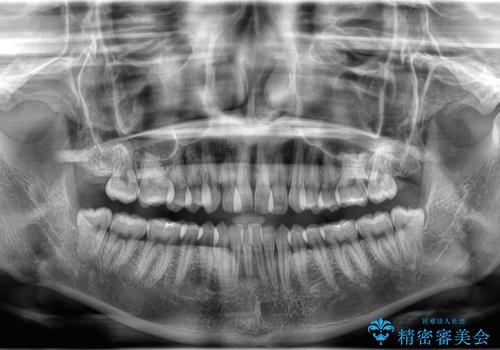

- 歯のデコボコ(叢生)を主訴にご来院された患者様です。

精密矯正検査を行った結果、歯を抜かずに行う、非抜歯のワイヤー矯正で治療を行う方針となりました。

歯並びの乱れに加え、**反対咬合(上下のかみ合わせのズレ)**も認められたため、見た目だけでなく、かみ合わせの改善も同時に行っています。